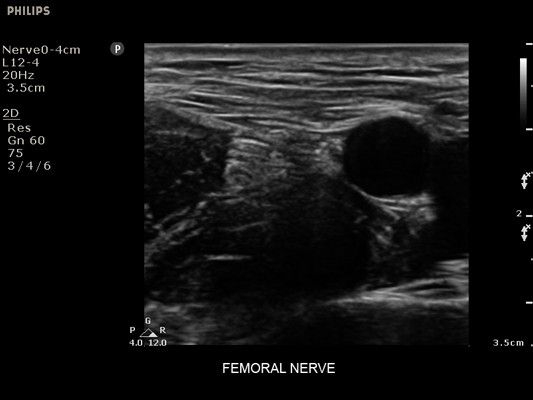

• Усиленная визуализация иглы без потери качества изображения окружающих тканей

• Сосудистый доступ

• Диагностика нервов

• Линейный УЗИ датчик Philips L12-4